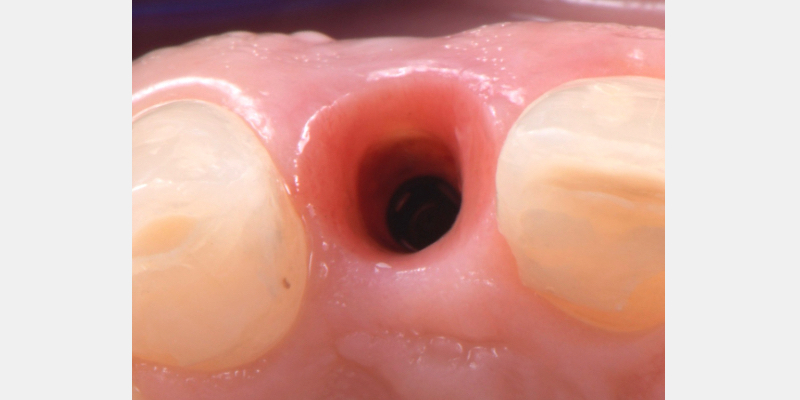

One of the most common complications with cement-retained implant restorations is inflammation around the crown. Excess cement can lead to peri-implant diseases such as peri-implant mucositis and even bone loss. A key factor to understand is the biological difference between teeth and implants — particularly the structure of the junctional epithelium and connective tissue — which makes removing residual cement around the restoration more difficult.

Here is a simple, step-by-step technique for fabricating a silicone jig to avoid excess cement in a cement-retained implant-supported restoration. It can be applied to a single crown or to an implant-supported cement-retained bridge.